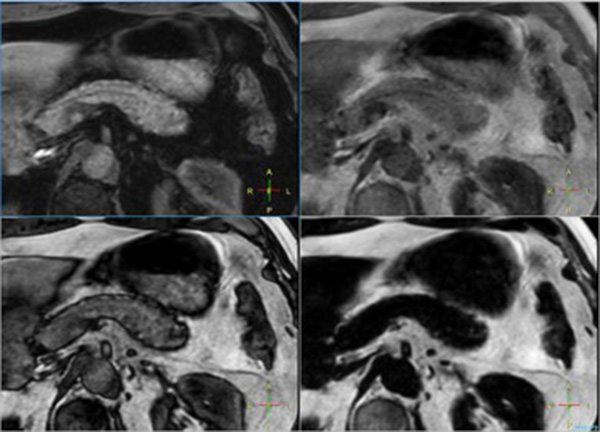

Pancreas imaging with dS Zoom